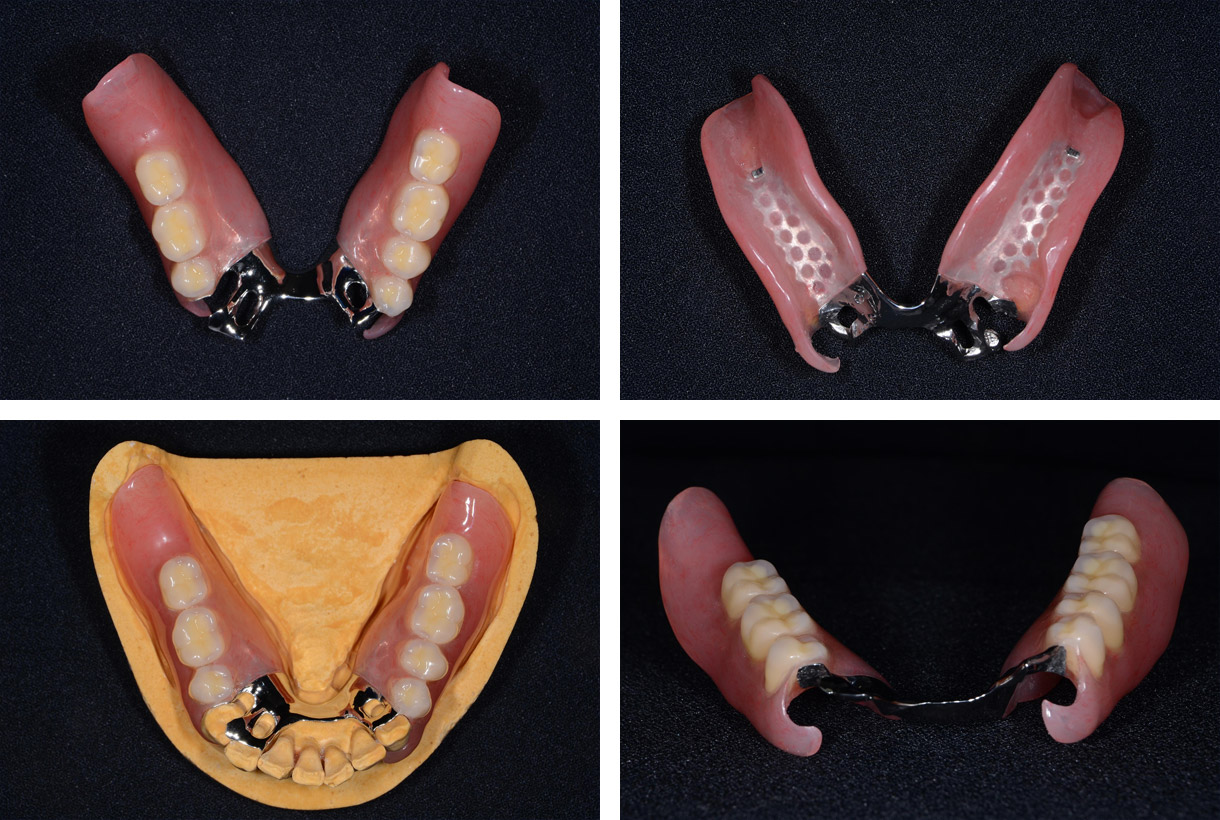

治療中②

抜歯した部位が治り、また患者様から見た目と異物感に対する訴えがあったため、ノンメタルクラスプ義歯を製作することとなりました。

金属床のため、前歯部は薄く、幅を狭くできました。歯ぐきを覆う必要がないため、歯周病の観点からも有利と言えます。

クラプスは樹脂を使用しているため、歯ぐきと同じピンク色です。樹脂のため、金属と比較すると変形しやすく、またその後の調整が難しいことがデメリットになります。

抜歯した部位が治り、また患者様から見た目と異物感に対する訴えがあったため、ノンメタルクラスプ義歯を製作することとなりました。

金属床のため、前歯部は薄く、幅を狭くできました。歯ぐきを覆う必要がないため、歯周病の観点からも有利と言えます。

クラプスは樹脂を使用しているため、歯ぐきと同じピンク色です。樹脂のため、金属と比較すると変形しやすく、またその後の調整が難しいことがデメリットになります。

全ての治療が終了後

全ての治療が終了した時点での写真になります。

本症例では、クラスプをかける歯の歯ぐきが左右とも少し下がっていたため、ノンメタルクラスプのピンク色の樹脂で歯ぐきのラインも綺麗に揃いました。

前歯部の異物感も審美性も解消され、患者様からは高い満足を得ることができました。